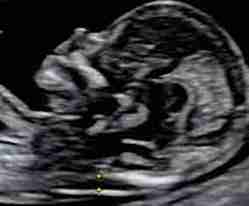

- İkili Test: Gebeliğin ilk trimesterinde (11-14. haftalar arası) yapılır. Anne kanındaki PAPP-A (gebelikle ilişkili plazma proteini A) ve serbest beta-hCG hormon düzeyleri ölçülür. Ayrıca, ultrason ile bebeğin ense kalınlığı (NT - nuchal translucency) değerlendirilir.

- İkili Test: 11-14. haftalar arasında yapılır. Ultrasonla ense kalınlığı ölçümü ve aynı gün veya yakın bir tarihte kan testi ile tamamlanır.